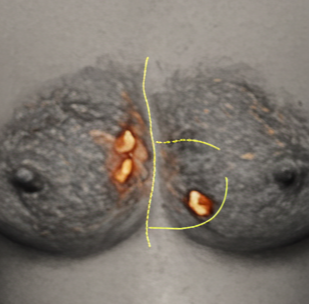

유두 변화: 유두가 함몰(들어가 보임)되거나, 피가 섞인 분비물이 나오거나, 젖꼭지 주변에 낫지 않는 습진이나 발진이 생길 수 있습니다.

피부 변화: 유방 피부가 오렌지 껍질처럼 두꺼워지거나, 움푹 들어가거나, 붉게 붓고 열감이 나타나는 염증성 유방암 증상도 있습니다.

한쪽 유방 크기나 위치 변화: 비대칭이 느껴지거나 모양이 달라질 때 주의가 필요합니다.